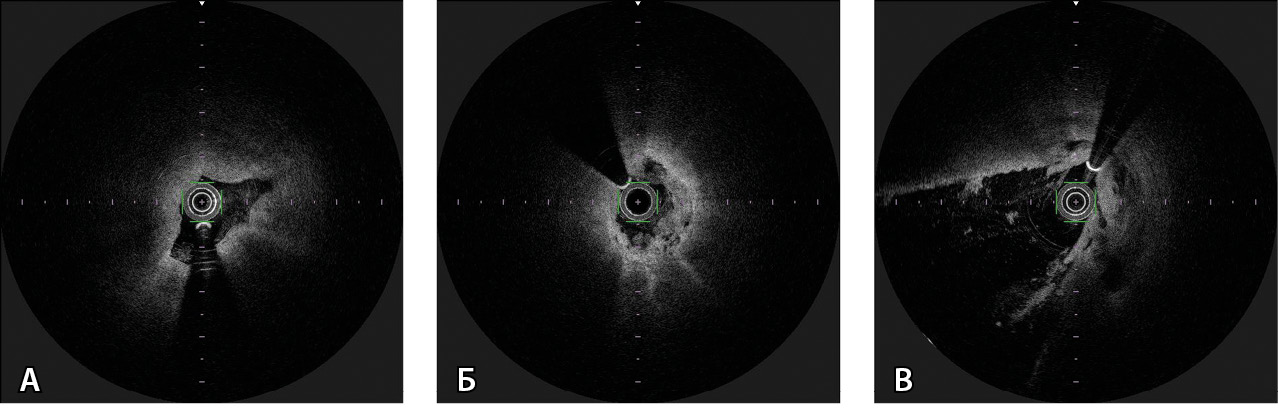

Рис. 1. Щипковая биопсия у пациента с опухолью Клацкина, Bismuth IV. А – рентгеноконтрастные изгибаемые/вращающиеся биопсийные щипцы Cordis BIPAL 7 F (2,33 мм) длиной 50 см. Б – холангиография с последующей щипковой биопсией опухоли общего печеночного протока из левого доступа. Видны раскрытые бранши щипцов. В – биопсийный материал. Фрагмент стенки желчного протока с разрастанием низкодифференцированной аденокарциномы (окраска гематоксилином и эозином; × 6)

Дальнейшее построение изображения на мониторе ОКТ занимало около 20 секунд. Выполняли оценку и интерпретацию полученных данных, сравнивая с результатами прямой холангиографии. При необходимости автоматическое исследование повторяли. Воспроизводили изображения двух видов: поперечный срез желчного протока из выбранного участка и «комбинированное изображение» продольного среза протока с миллиметровой шкалой для облегчения навигации. Глубина изображения составляла 1–2 мм, что соответствовало визуализации микроструктуры стенки желчного протока с разрешением до 10 мкм. Признаками злокачественного процесса считали выраженное нарушение слоистости структуры и/или наличие множества гипорефлекторных зон неправильной формы (рис. 2).

Рис. 2. Оптическая когерентная томография: поперечные срезы желчного протока в норме и при опухолевых стриктурах. А – неизмененная стенка холедоха. Желчный проток спавшийся, щелевидной формы с четкими стенками и слоями. Б – признаки злокачественной стриктуры: сужение просвета, выраженное нарушение слоистости и наличие множества гипорефлекторных зон неправильной формы. В – гипержелезистая слизистая оболочка холедоха, характерная для опухоли Клацкина